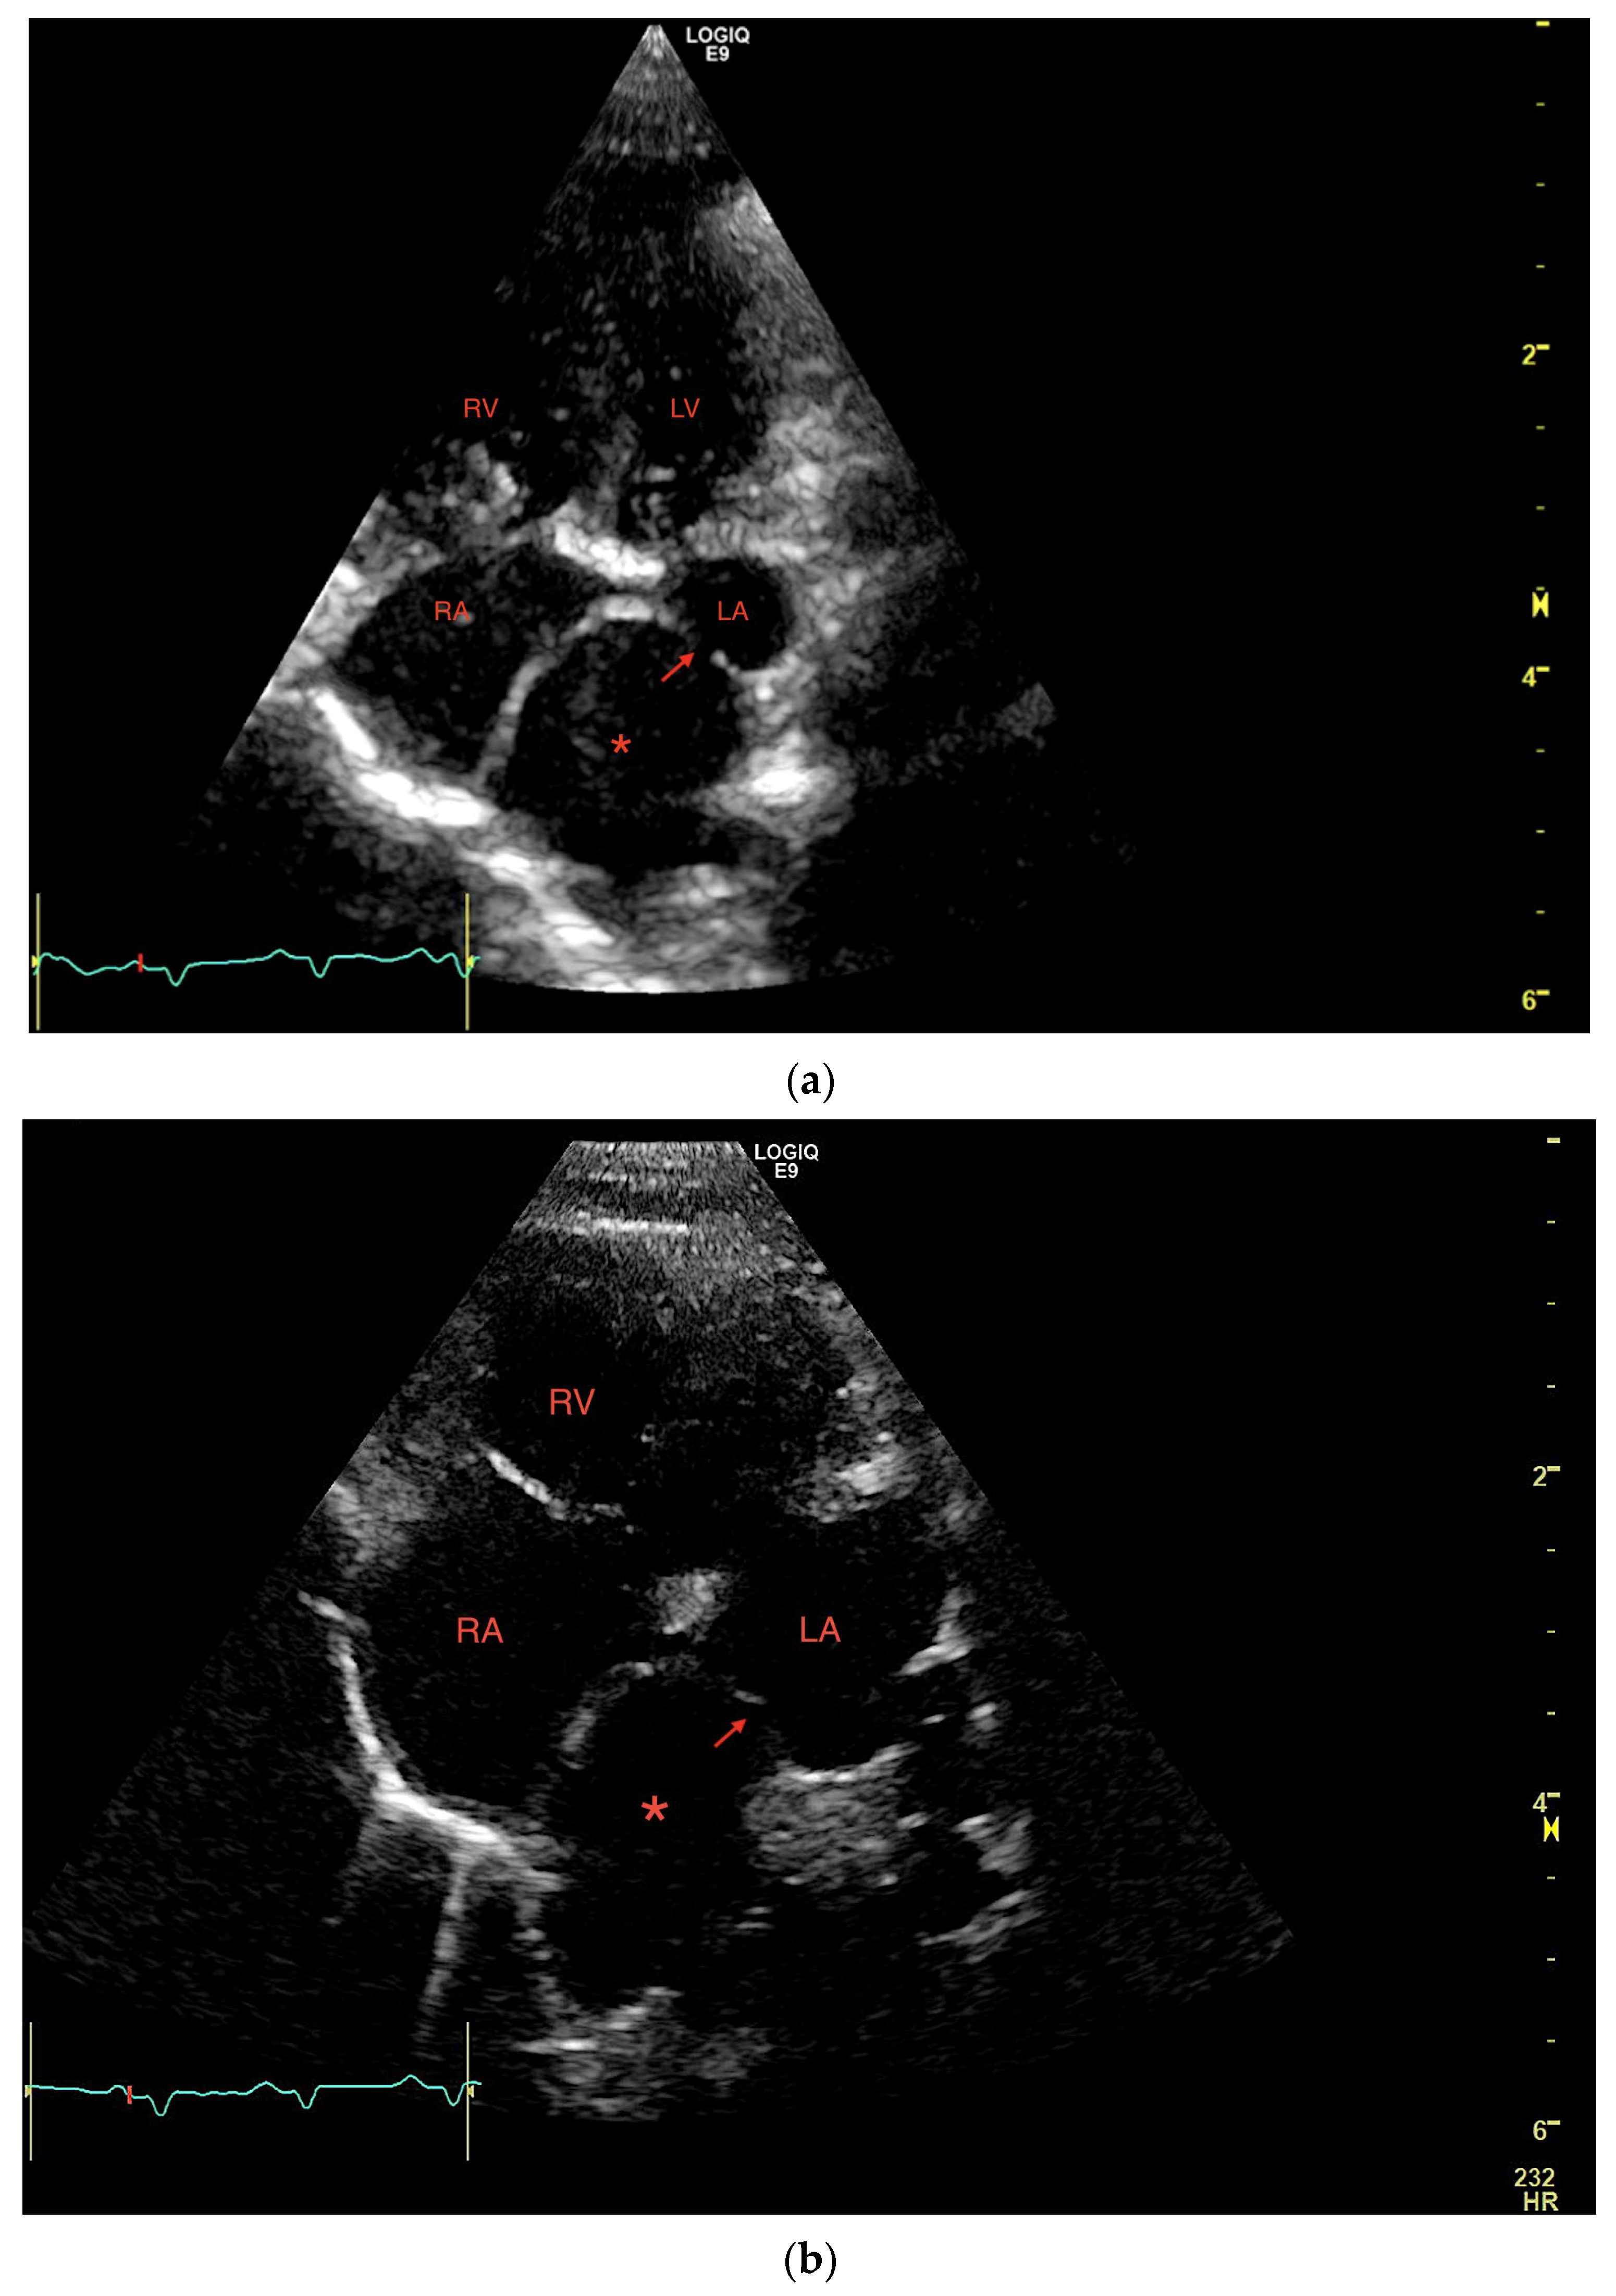

1. Case Description